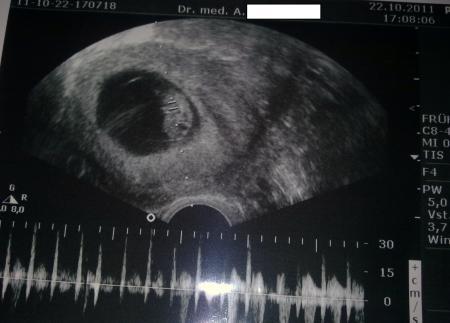

Habt ihr den Stein um 17:08 Uhr plumpsen hören? Mit dem Zwerg ist alles in Ordnung!!! Als sie dann das Herzchen hörbar gemacht hat liefen einfach die Tränen vor Erleichterung. habe dann gleich auch noch meinen Mutterpass bekommen und ich wurde über die NTM aufgeklärt.Sie sagte es ist von ihrer Seite auch hier alles i.O. aber wenn ich es doch aufgrund meines Alters noch genau abgeklärt haben möchte muss ich es mir überlegen, Adressen habe ich mitbekommen. Würde mich 140€ kosten... Ich bin sooo froh, das alles i.O. ist... Nun muss ich am 14.11. wieder hin, weil sie meint wir machen lieber in 3 Wochen, weil mit 4 Wochen sicher zu lang sind nach dem Erlebnis heute... Ich find das echt klasse von ihr, weiss schon, warum ich seit 17 jahren dort bin... LG und danke für eure Daumen, sind Gold wert

Bild zu